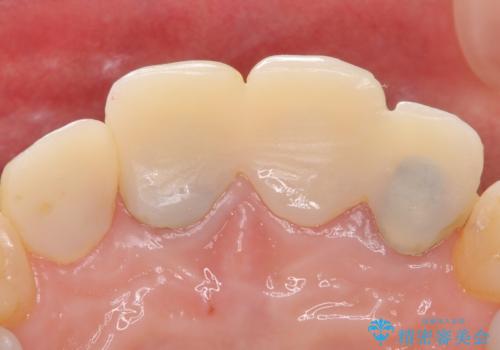

自然な前歯にしたい ジルコニアクラウンでの修復

- 前歯を綺麗にしたいとのことで来院されました。

色調・適合ともに改善するために一度被せ物を外し、歯の形を整えた後に新しい被せ物を装着していきます。

歯ぐきの炎症を抑えつつ、被せ物と歯との境目がわからなくなるよう被せ物を装着しました。

審美性が大変改善されたことで患者様にもご満足いただけました。